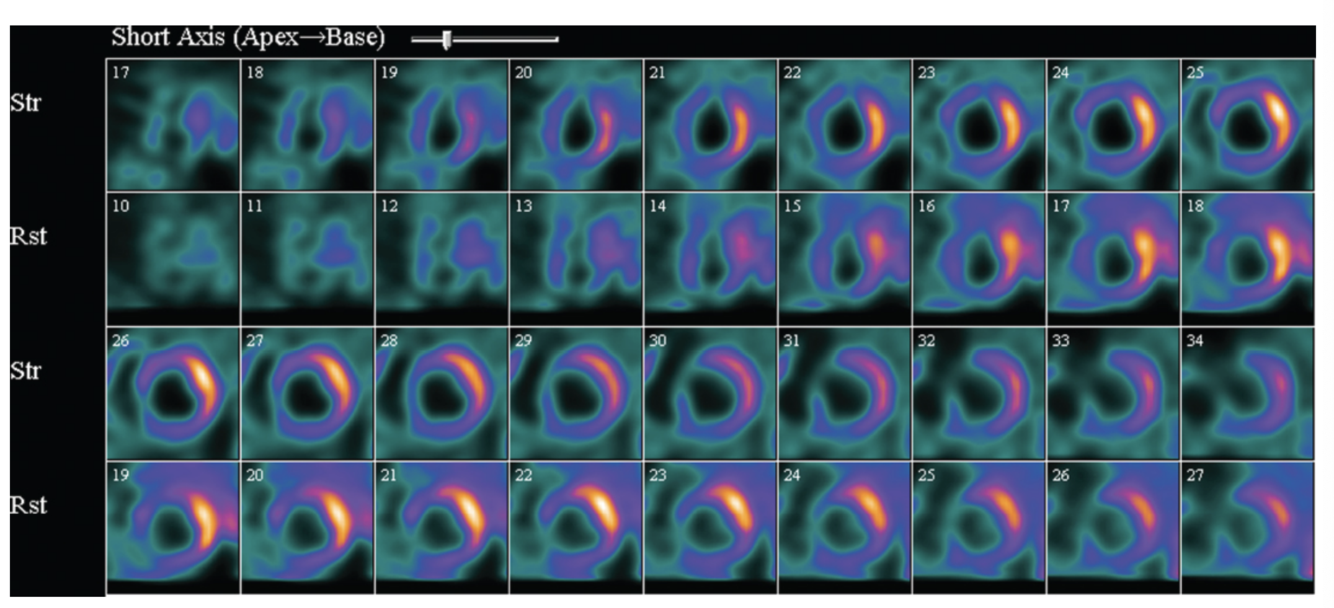

Describe the findings:

severe lateral wall ischemia and apical infarction